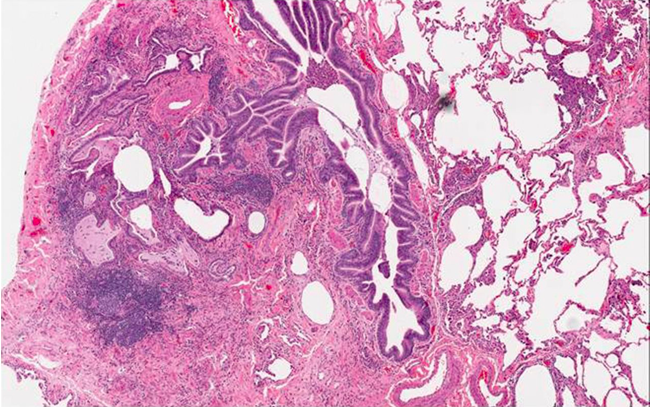

Scleroderma plaque fibrosis facial lesions

Scleroderma plaque fibrosis facial lesions 112 photos